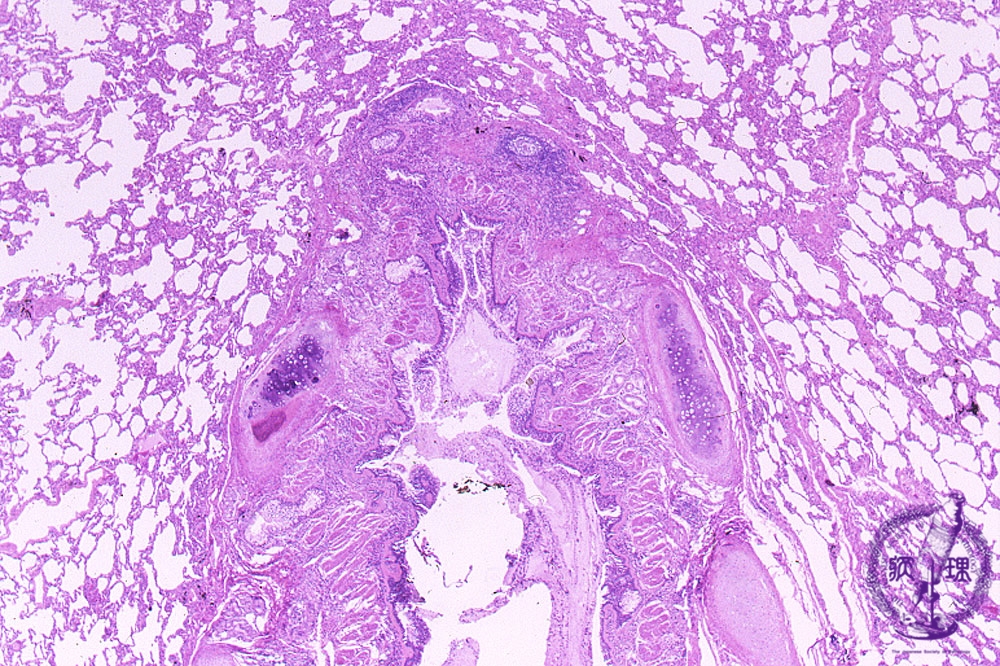

- 5.Lung, Pleura

- (6)Bronchial asthma

Microscopic view (HE stain, low power view): Bronchial wall smooth muscle (red arrow) proliferates with thickening of the entire bronchial wall. Mucus retention (blue arrow) is noted within the bronchial lumen.